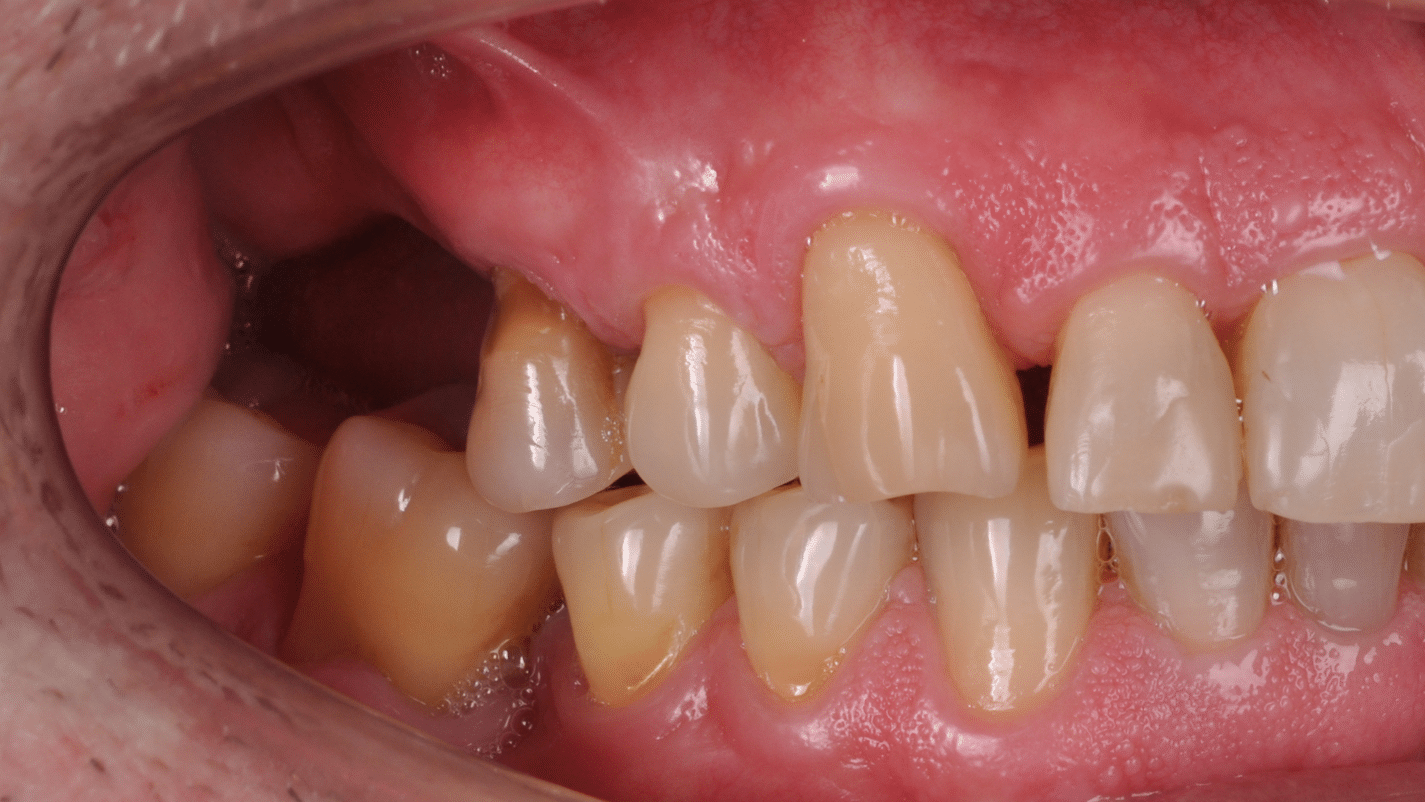

Doar astfel putem crea profilul de emergență corect al coroanei dentare, ceea ce permite conformarea papilei și a sulcusului.